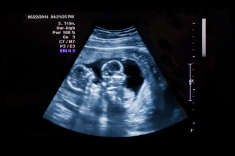

Ecográficamente se observará su talla midiendo la longitud desde corona a rabadilla, pues es difícil que el feto pueda extender los miembros inferiores, algo que orientará al ginecólogo sobre el crecimiento de vuestro futuro hijo. Grosso modo podemos indicar que durante las siguientes semanas se presentarán una serie de cambios, por ejemplo, en la 12ª sg (semana de gestación) la longitud fetal es de 6 a 7 cm, observándose los dedos, el desarrollo de las uñas y la piel, mostrando los genitales signos del sexo que tendrá el futuro neonato.